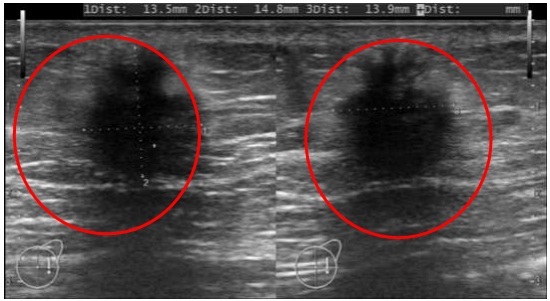

Hình ảnh siêu âm tuyến vú cho thấy có nốt giảm âm vú phải vị trí 12h, cách núm vú 5cm, kích thước 13,5×14,8×13,9mm (Ảnh: Bệnh viện cung cấp).